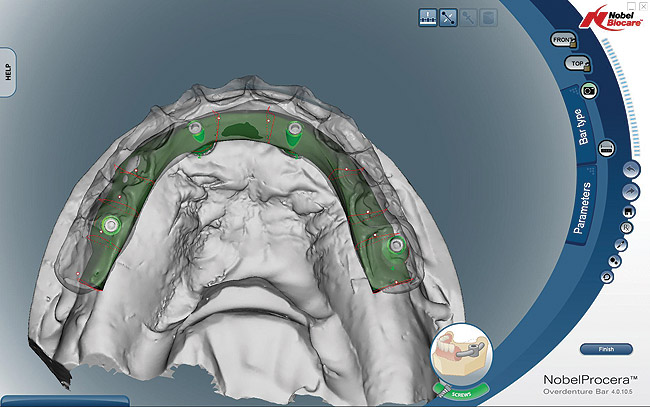

The laboratory technician made a small triad base-plate using at least two titanium provisional sleeves into the base plate. This allowed the restorative dentist to stabilize any required intermediate tooth try-ins. The teeth were set up, and a wax-up of the facial contours was produced. The facial and lingual contours of the wax-up were created as an exact replica of the finished product. The teeth were removed from the wax-up leaving a negative of the denture teeth in the wax around the arch. The master cast and baseplate without the teeth were forwarded to Nobel Biocare for scanning. Due to the fact that this particular technique and the implants can accommodate a wide range of prosthetics and abutments, high-strength zirconia or titanium substructures can be fabricated using CAD/CAM technology (Figure 8 and Figure 9).10,11 Therefore, the bar was designed on screen considering support for each tooth, and then it was milled and returned to the laboratory.

Figure 8  Upper and lower arch design of CAD/CAM titanium frames.

Figure 8

Figure 9  Upper and lower arch design of CAD/CAM titanium frames.

Figure 9